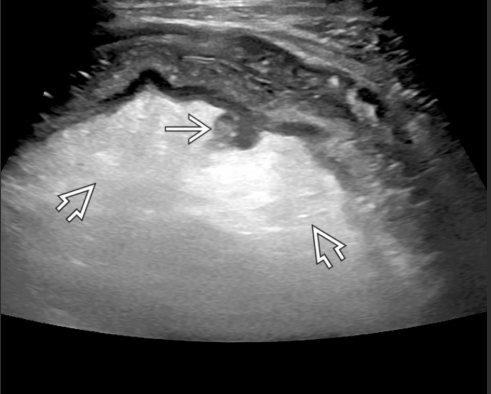

A maioria dos pacientes com diverticulose tem doença no cólon ______(direito/esquerdo), porém a do cólon _______(direito/esquerdo) é frequente em pacientes asiáticos (43%-50%).

Esquerdo; direito.

Diverticulose cólica (seta reta). Hipertrofia da camada muscular (seta curva)